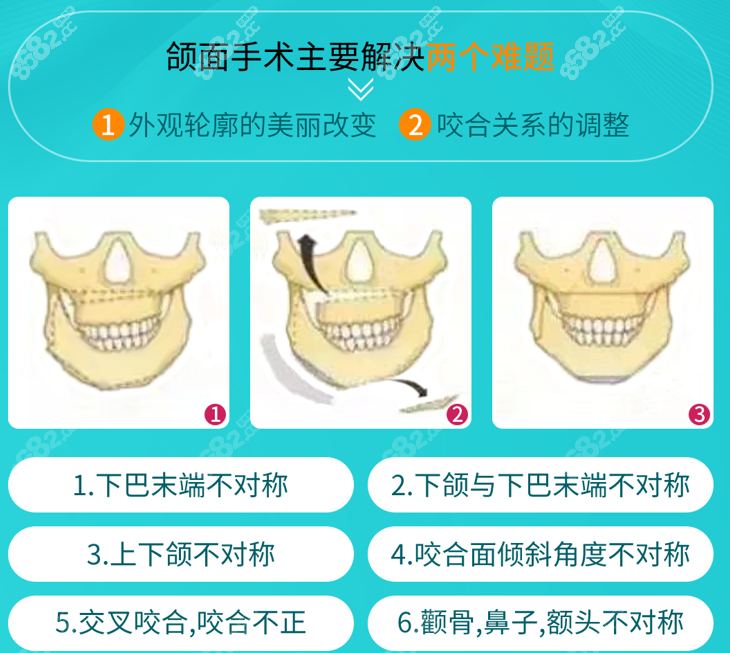

广州广大医院双鄂手术费用是6w起便宜,如果是凸嘴、龅牙、地包天、小下巴、凸嘴伴小下巴、月亮脸等牙颌面畸形问题都可以来广州广大医院做双鄂手术,8#682小编温馨提醒大家广大医院双鄂手术费用和每个人颌面畸形情况有关,以面诊医生告知的价格为准。